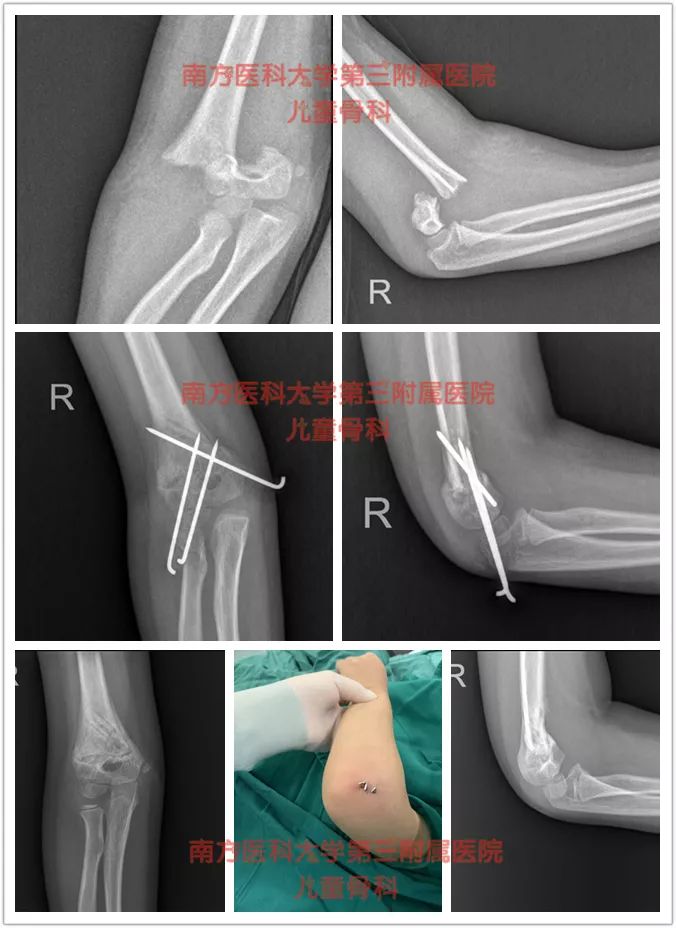

我科近乎“0”切开几率方式处理肱骨髁上骨折,麻醉下采用手法复位,克氏针交叉固定+石膏固定术,显著的减少了常规保守治疗肱骨髁上骨折高达30%的畸形率。

Ⅱ型*特中**殊的中尺侧有压缩的要手术治疗,复位不好容易往往导致畸形愈合,形成肘内翻。要先手法整复、经皮克氏针固定一个月,纠正畸形,维持坚强的内固定。

Ⅲ型这种程度就比较复杂和严重得多,也是需要要手术治疗,闭合复位,经皮克氏针固定。

病例1